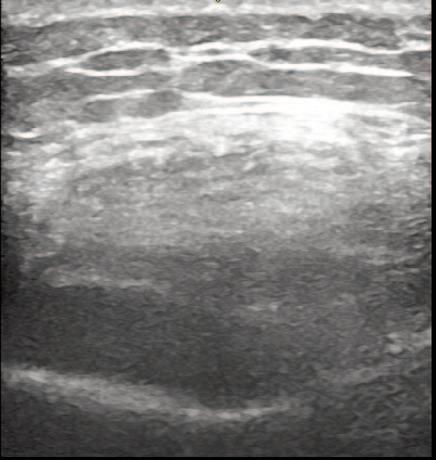

The Use of MSK Ultrasound with Quadriceps Muscle Injury.

Manske R, Voight M, Wolfe C, Page P.